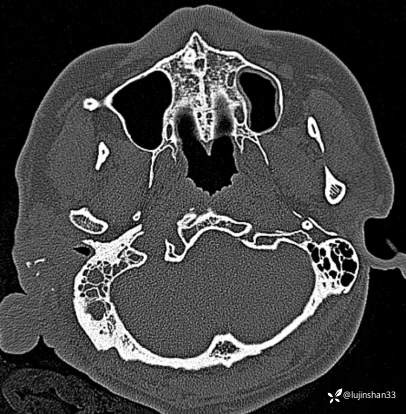

(2023-02-17 17:52,本院)行CT(血管心脏)检查提示:1、右侧耳颞部异常改变,考虑血管瘤可能,可见粗大供血动脉及引流静脉,局部动静脉瘘可能,右侧颈外动脉分支增粗,请结合临床及相关检查。2、左侧颈内动脉粥样硬化,管腔轻微狭窄,请结合临床。血管外科会诊意见:CTA示右颈外动脉起始部结扎后闭塞,介入栓塞暂无合适入路;

临床诊断:耳廓、颞骨蔓状血管瘤合并出血